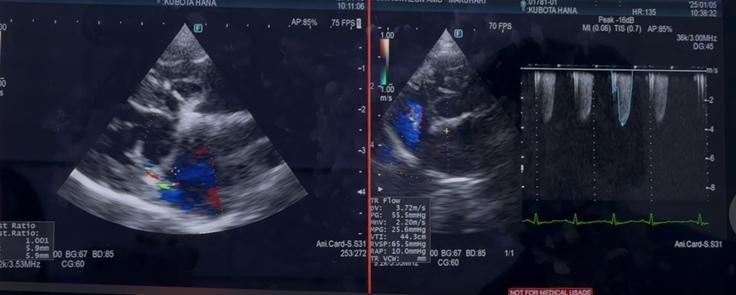

心臓手術後 1年8ヶ月検診でした

先日心臓手術後、1年8ヶ月検診でした

エコー上は、逆流は相変わらず残っていますが…

少量であり、悪化はみられませんでした

左心の大きさも、変わらず…

小さくはなっていませんでした

右心の三尖弁の逆流と肺高血圧症も、変わらず…中等度でした…

抗血栓薬は、継続です…

緊張で、呼吸音が大きいせいもあるけど

今回は、心雑音は聴こえないとの事でした🙌

術前レベル5だった心雑音が、今では1になりました✨